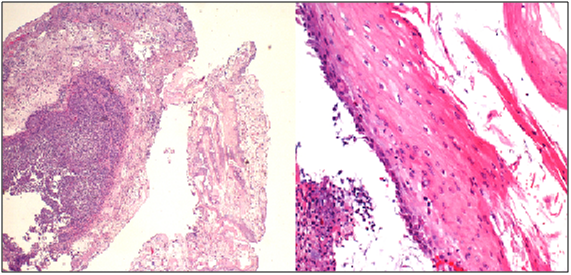

Symptoms recurred despite compliance with therapy and EGD two months later showed persistent LA Class D esophagitis without histologic evidence of opportunistic infection. A bariums wallow showed a tight 3cm long, 4 mm diameter stricture in the same location (Figure 2). Given the unusually refractory nature and mid-esophageal location of his circumferential esophagitis and stricture and no histologic evidence of Barrett’s, opportunists, or neoplasia, MMF was suspected to be the culprit. His MMF was discontinued and azathioprine was substituted. He was re-dilated to 12 mm using a through the scope (TTS) balloon. Barium swallow (Figure 3) at 3-month follow-up showed no evidence of esophagitis or stricture and PPI therapy was discontinued without symptomatic recurrence. At 2.5 year follow up he continues to be symptom free off of PPI therapy.

Figure 2 Barium swallow in November 2013 showed a tight 3 cm long, 4 mm diameter stricture in the lower third of the esophagus.